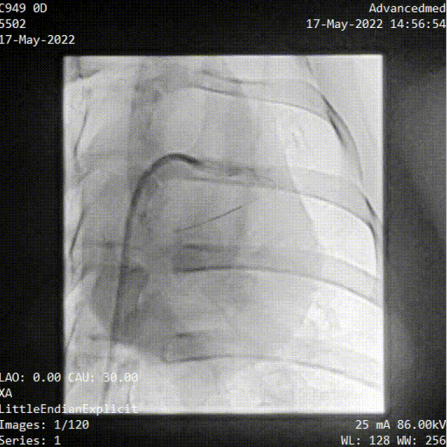

(睿心血管介入手術(shù)機器人從端操作)

參與此次動物實驗的臨床主任醫(yī)師——中山大學(xué)附屬第七醫(yī)院特聘教授、復(fù)星醫(yī)療集團心血管技術(shù)總監(jiān)彭宇程向億歐大健康介紹道,“本次動物實驗中,我們用機器人輔助完成了PCI、腎動脈支架植入以及下肢血管覆膜支架(由深圳創(chuàng)心醫(yī)療提供)植入等3種常見血管介入手術(shù)類型,說明了這個平臺的兼容性還是挺好的,同時在手術(shù)中,導(dǎo)絲導(dǎo)管操作、球囊支架輸送都能夠順利實施?!?/p>